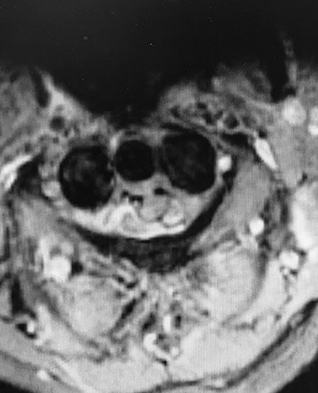

Figures 1 through 3 show sagittal and axial MRIs and a radiograph from a

77-year-old woman with leg pain when standing and walking of 1 year duration. The pain improves when she leans forward. She has been in physical therapy, taken oral analgesics, and had epidural injections with minimal relief. What is the best next step?

The patient has lumbar stenosis of L2-3 and L3-4. She has no spondylolisthesis or instability. For her condition, spinal fusion plays a minimal role. She has no evidence of instability, and her condition can be addressed through laminectomy only. No role exists for microdiskectomy, because her disease results from a combination of ligamentum flavum hypertrophy and facet hypertrophy.